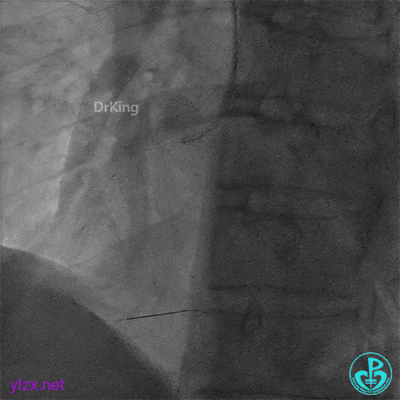

支架近端植入3.5×13mm支架覆盖夹层。

最后结果示右冠脉近端支架外仍然可见夹层。